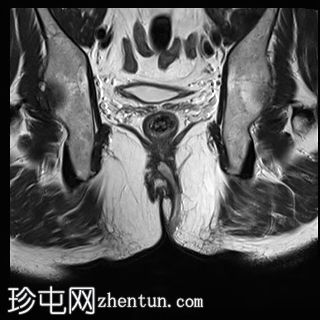

冠状位

T1时间

位于5点钟和6点钟位置之间,在STIR和T2加权图像上呈高信号。

瘘管起源于括约肌间平面附近,穿过肛门内外括约肌,并延伸至左侧坐骨肛门窝。瘘管内充满液体信号,周围有轻微水肿。肛提肌上方未观察到颅骨延伸。

根据圣詹姆斯大学医院的磁共振分类系统,该病例被归类为III级左侧肛周经括约肌瘘,左侧坐骨肛门窝可见炎症改变。